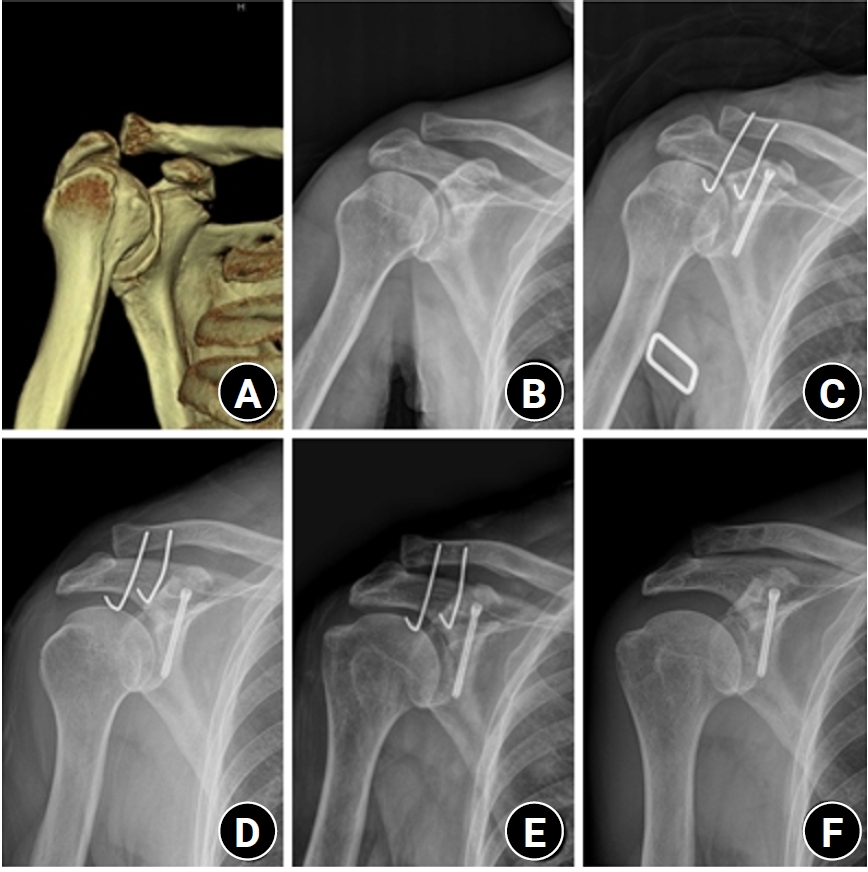

If adequate compression could not be achieved with screw fixation alone, the ACJ was first stabilized with a locking compression hook plate (clavicle hook plate; DePuy Synthes). After sufficient relaxation of the coracoclavicular ligament was ensured, screw fixation was repeated to obtain firm compression at the fracture site. Postoperative radiographs were obtained to assess fracture reduction and fixation (Fig. 1).

Fig. 1.

(A, B) Initial shoulder anteroposterior (AP) radiograph and three-dimensional computed tomography images of a 33-year-old male patient show a coracoid process fracture associated with an acromioclavicular joint (ACJ) injury. (C, D) Immediate postoperative C-arm images demonstrate open reduction and internal fixation using a 3.0-mm headless compression screw (HCS) for the coracoid process fracture and a clavicle hook plate for the ACJ injury. (E, F) Immediate postoperative shoulder AP and scapular Y radiographs show fixation using a 3.0-mm HCS for the coracoid process and a clavicle hook plate for the ACJ injury. (G, H) Postoperative 2-month AP and scapular Y radiographs show union of the coracoid process. (I–L) At the final follow-up, the patient demonstrated satisfactory radiographic and clinical outcomes, including full active range of motion.

Fig. 1. (A, B) Initial shoulder anteroposterior (AP) radiograph and three-dimensional computed tomography images of a 33-year-old male patient show a coracoid process fracture associated with an acromioclavicular joint (ACJ) injury. (C, D) Immediate postoperative C-arm images demonstrate open reduction and internal fixation using a 3.0-mm headless compression screw (HCS) for the coracoid process fracture and a clavicle hook plate for the ACJ injury. (E, F) Immediate postoperative shoulder AP and scapular Y radiographs show fixation using a 3.0-mm HCS for the coracoid process and a clavicle hook plate for the ACJ injury. (G, H) Postoperative 2-month AP and scapular Y radiographs show union of the coracoid process. (I–L) At the final follow-up, the patient demonstrated satisfactory radiographic and clinical outcomes, including full active range of motion.